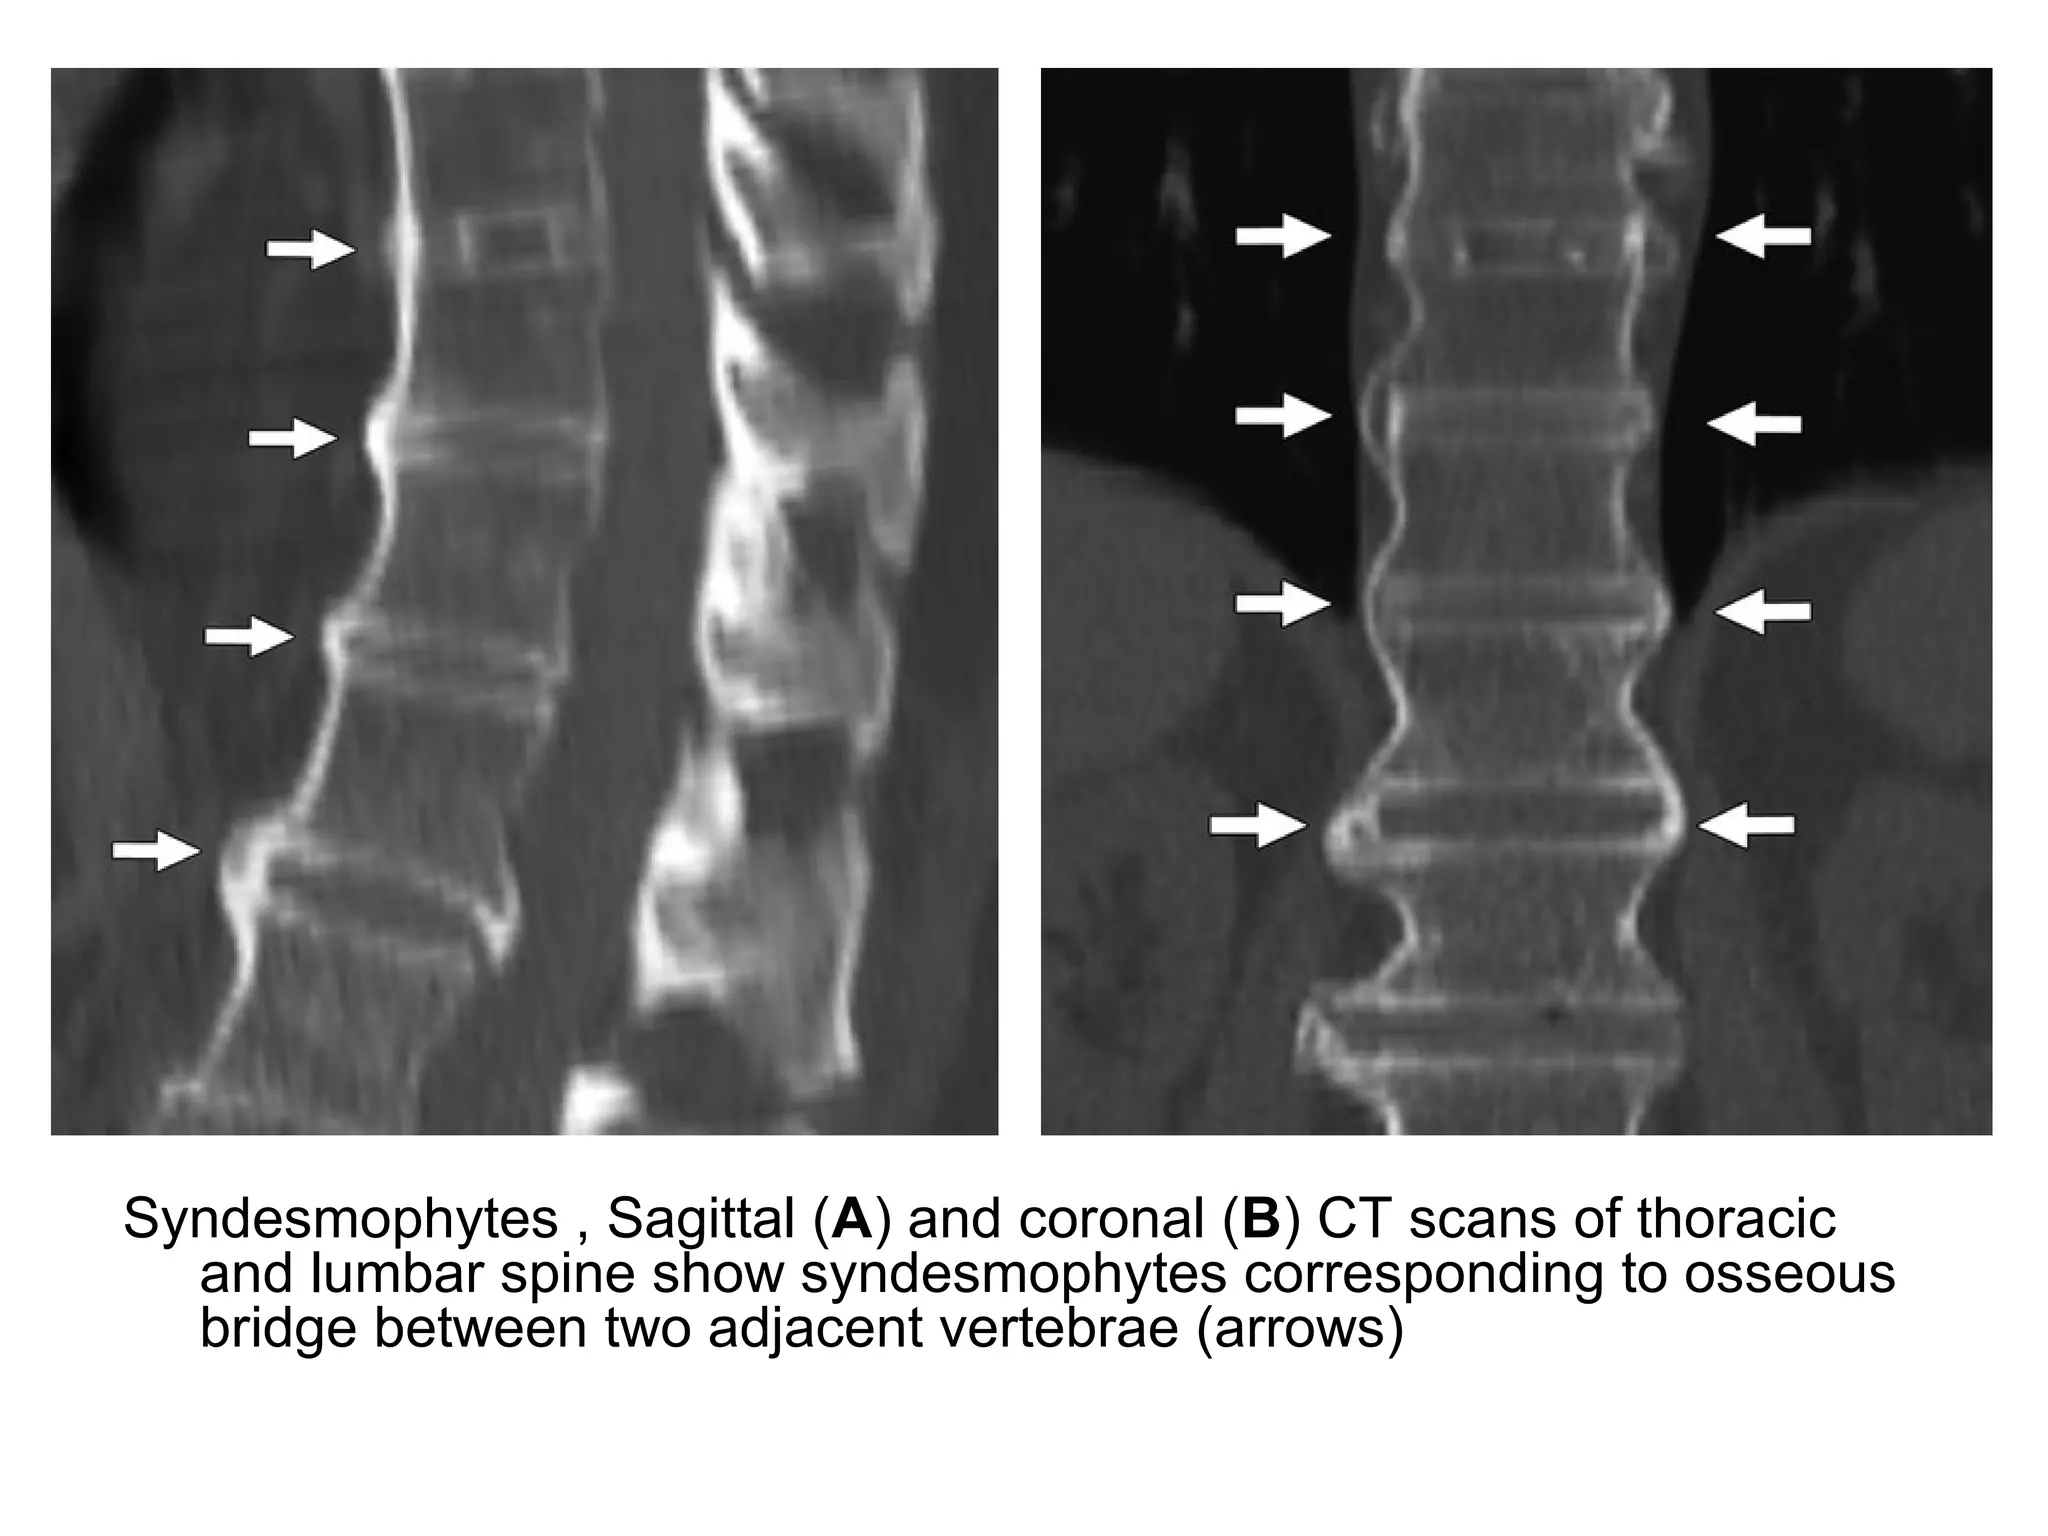

3-The last stage of spinal involvement consists of :

-Syndesmophytes , consisting of bone outgrowth forming

an osseous bridge between two adjacent vertebrae

(these bone formations are different from osteophytes

because their initial directions are not horizontal but

vertical)

-Syndesmophytes (end stage of Romanus spondylitis) are

responsible for the development of peripheral spinal

ankylosis

Syndesmophytes , Sagittal (A) and coronal (B) CT scans of thoracic

and lumbar spine show syndesmophytes corresponding to osseous

bridge between two adjacent vertebrae (arrows)